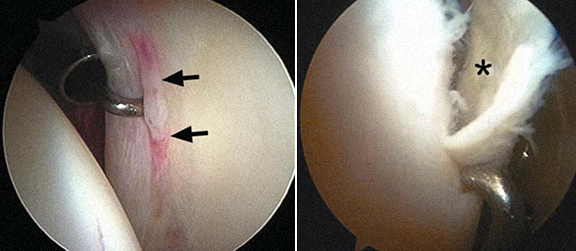

1 - Rotura do labrum 2 – Delaminação da cartilagem